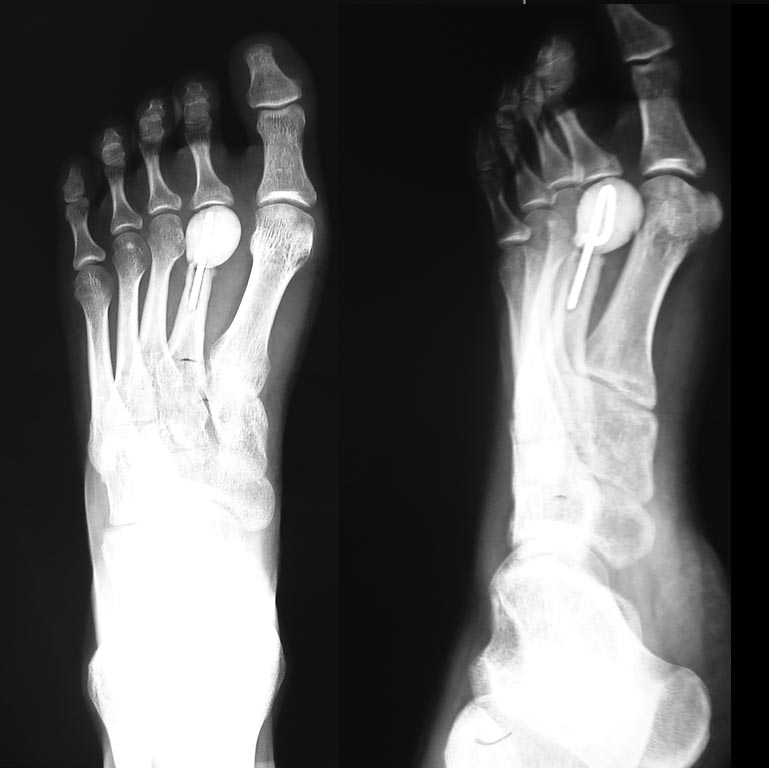

Здравствуйте, коллеги. К нам обратилась пациентка, девушка 1990 г р с жалобами на боли в стопе. На Р-снимках замещенный дефект головки 2-й плюсневой кости цементным спейсером и спицей.

По видимому ранее ей оперировали Келера 2. Думаю, что боли возникают из-за нестабильности спицы в костно-мозговом канале 2 ПК.

У этой пациентки было полное разрушение головки и шейки 2-й плюсневой кости, установка цементного спейсера на спице было мерой замещения костного дефекта. Но эта мера неэффективна, так как сохраняется болевой синдром. На Р-снимках видна резорбция костной ткани в области стояния спицы